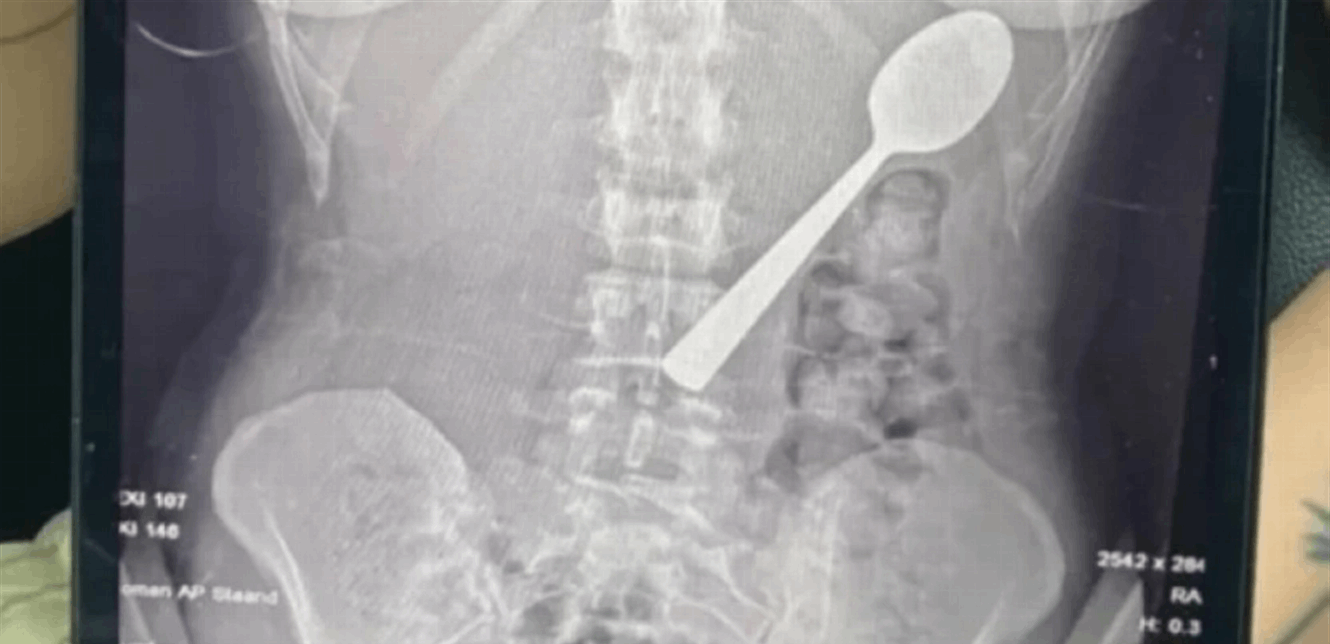

تحولت لحظة عشاء عادية داخل منزل في بلجيكا إلى حالة طبية نادرة، بعدما ابتلعت شابة ملعقة بطول 17 سنتيمتراً دفعة واحدة إثر قفزة مفاجئة من كلبها أثناء تناولها الطعام.

وعند مراجعة الأطباء، تبيّن أن الملعقة أكبر من أن تمر عبر الجهاز الهضمي بشكل طبيعي، ما استدعى تدخلاً عاجلاً. وبعد انتظار يومين تحت المراقبة، خضعت ريمي لعملية منظار معدة تحت التخدير الموضعي، حيث قام الأطباء بتدوير الملعقة بحذر داخل المعدة لسحبها، ما تسبب بنزيف طفيف والتهاب مؤقت في الحلق.